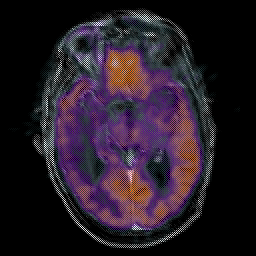

Glioma Overlay -- Slice #9

[Home][Help][Clinical] Slice 9